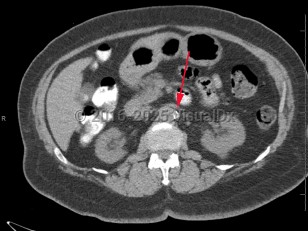

Imaging Studies image of Renal artery stenosis - imageId=8361094. Click to open in gallery.  caption: '<span>Axial image from unenhanced CT scan of the abdomen demonstrating dense calcifications at the take off of the left renal artery, consistent with severe stenosis.</span>'

Axial image from unenhanced CT scan of the abdomen demonstrating dense calcifications at the take off of the left renal artery, consistent with severe stenosis.